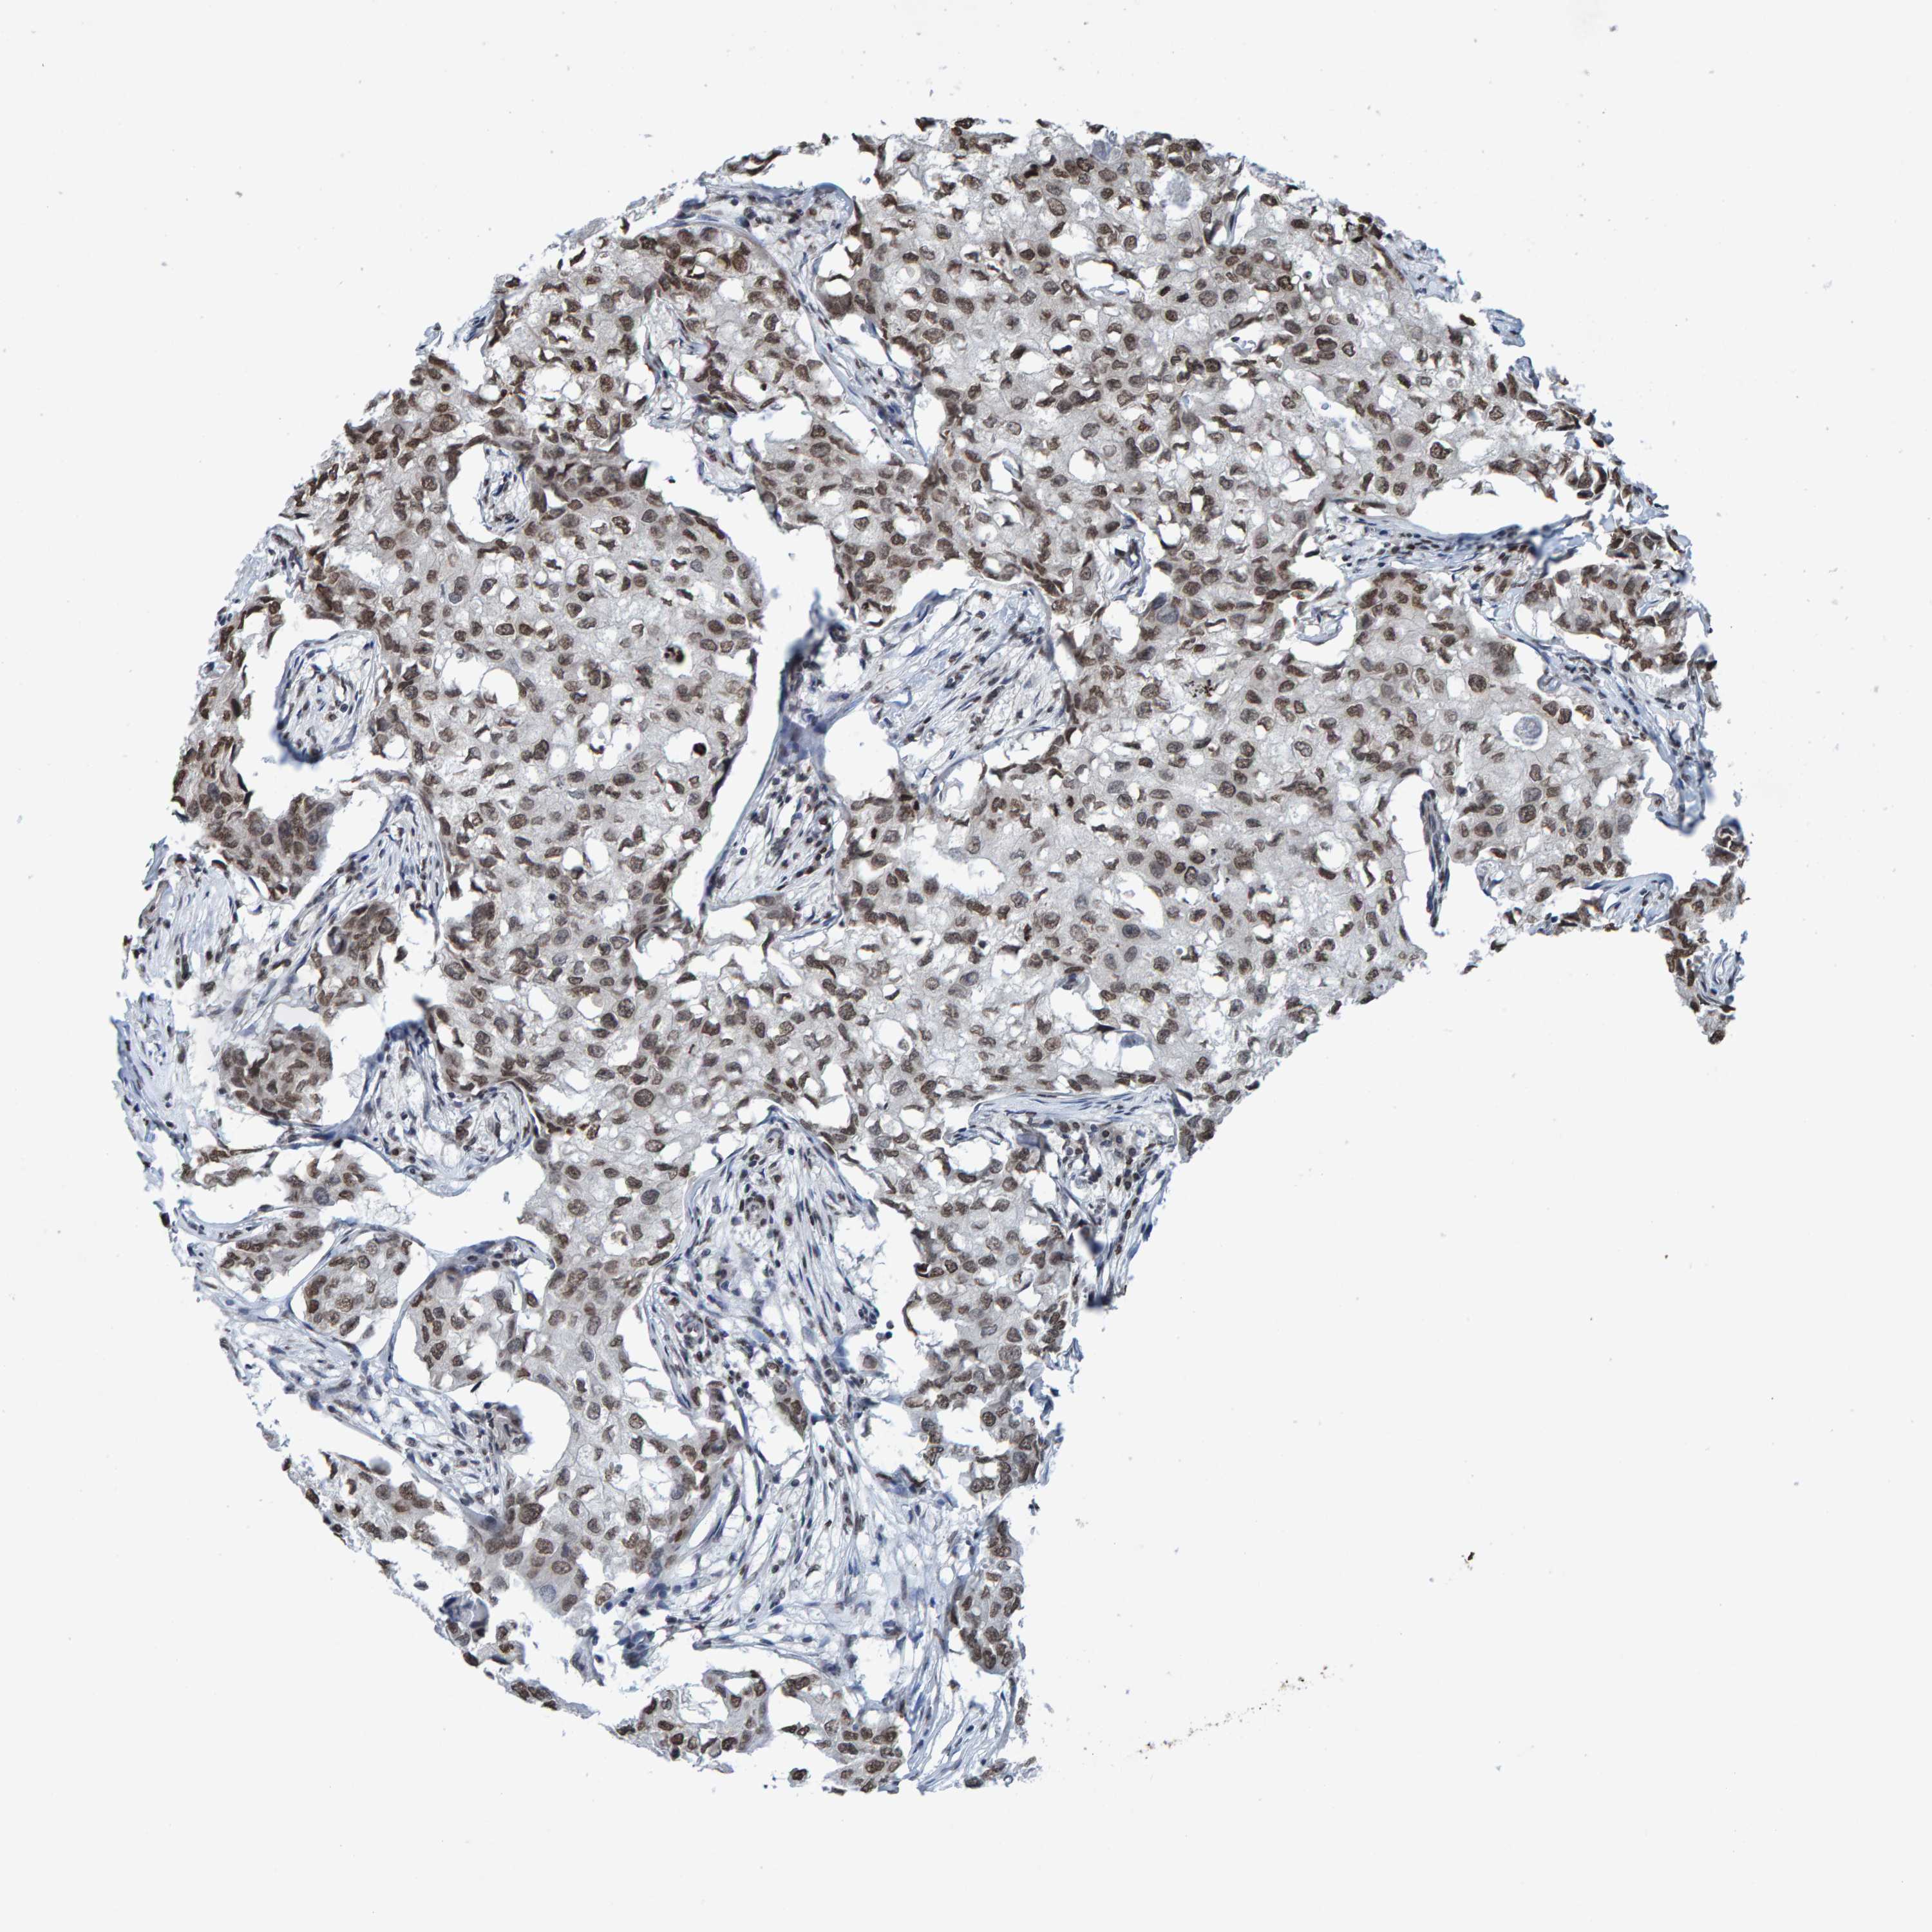

CANCER BREAST CANCER Show tissue menu

BRCA TCGA BRCA VALIDATION PROTEIN EXPRESSION